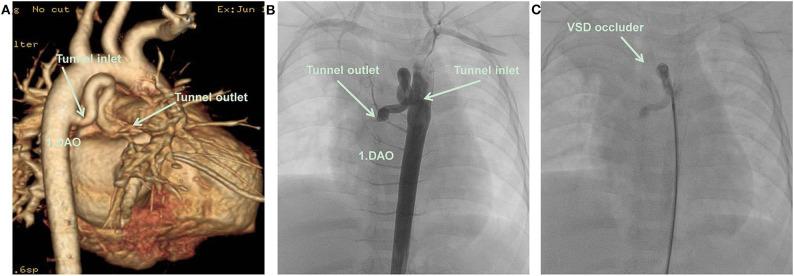

Congenital descending aorta-right atrial tunnel is a rare congenital heart defect. Herein, a new case successfully treated by transcatheter closure using a new type of ventricular septal defect occluder from the aortic side was reported. An 11-month-old Chinese girl presenting with a cardiac murmur was suspected with partial anomalous pulmonary venous connection as assessed by echocardiography. Descending aorta-right atrial tunnel was confirmed by computed tomography angiography and cardiac catheterization. Subsequently, transcatheter closure was performed successfully using a new type of ventricular septal defect occluder from the aortic side. The cardiac murmur disappeared after the intervention, and echocardiography did not reveal any abnormal flow inside the right atrium. At 6 months, the patient had no murmur, and no residual shunt was found using the echocardiogram. Descending aorta-right atrial tunnel is a rare anomaly. Transcatheter closure was successful in our case. Long-term follow-up is needed to assess any progressive growth of the residual tunnel.

先天性降主动脉-右心房通道是一种罕见的先天性心脏缺陷。在此,报告了一例使用新型室间隔缺损封堵器经导管从主动脉侧成功封堵的新病例。一名11个月大的中国女童因心脏杂音就诊,经超声心动图评估怀疑为部分性肺静脉异位连接。计算机断层血管造影和心导管检查证实为降主动脉-右心房通道。随后,使用新型室间隔缺损封堵器经导管从主动脉侧成功进行了封堵。干预后心脏杂音消失,超声心动图未显示右心房内有任何异常血流。6个月时,患者无杂音,超声心动图未发现残余分流。降主动脉-右心房通道是一种罕见的异常情况。我们的病例经导管封堵成功。需要长期随访以评估残余通道是否有任何渐进性生长。